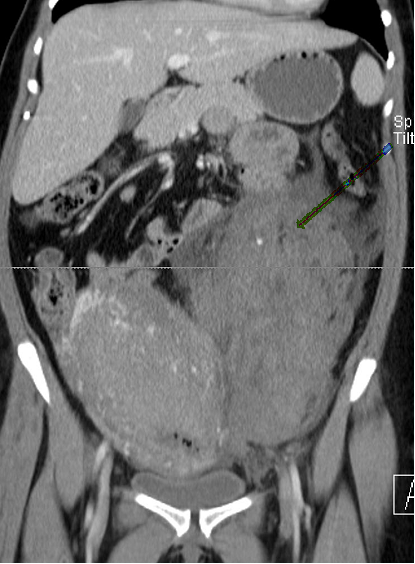

Laboratory tests including complete blood count and coagulation profile were sent. There was a suspicion of retroperitoneal fluid collection on Focused Assessment with Sonography in Trauma (FAST) ultrasound examination of the abdomen. The endometrial thickness was noted to be 0.7 cm. The hemoglobin and hematocrit obtained were 8.6 gm/dl and 26%, which were significantly decreased from 11.9 gm/dl and 36.3% at the time of admission. The coagulation profile was normal with an INR of 1.0. Transfusion of two units of packed red blood cells was started, and a contrast-enhanced computed tomography (CT) scan of the abdomen and pelvis was obtained. The CT showed a large amount of complex fluid in the pelvis extending caudally along the left retroperitoneum to the level of the upper left renal pole with a mass effect on the uterus and left kidney (Figure 1 & 2). The collection contained a prominent, tortuous left ovarian artery coursing through the hematoma with a contrast-filled outpouching measuring 1.6 cm in the mid-portion of the artery which was suspicious for pseudo-aneurysm.

Figure 1 Coronal image of CT abdomen and pelvis demonstrates a large left pelvic and retroperitoneal hematoma extending up to the level of the kidney with mass effect on surrounding structures.